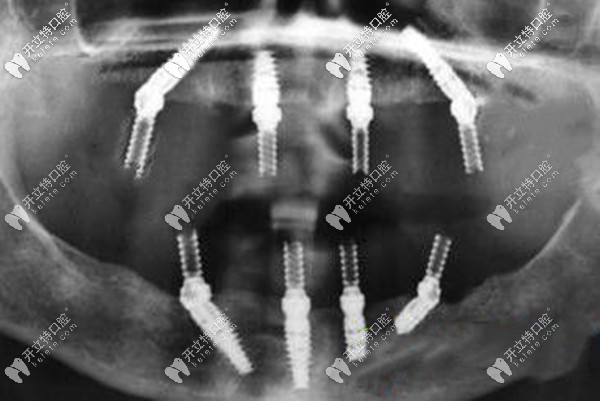

如果,牙槽骨量不足,做ALL-ON-4全口即刻負(fù)重種植牙,不用植骨,上下頜各植入4顆種植體就能恢復(fù)全口的咀嚼功能,而且是當(dāng)天種牙當(dāng)天就能吃東西。

一般做all-on-4種植牙需要導(dǎo)板,而適合的種植體只有韓系和瑞典諾貝爾,年齡較大的可以選擇性價(jià)比高的韓系植體,半口的價(jià)格大概7萬起、全口13萬起;年輕或不差錢的就用瑞典諾貝爾種植體,半口16萬起、全口28萬起。